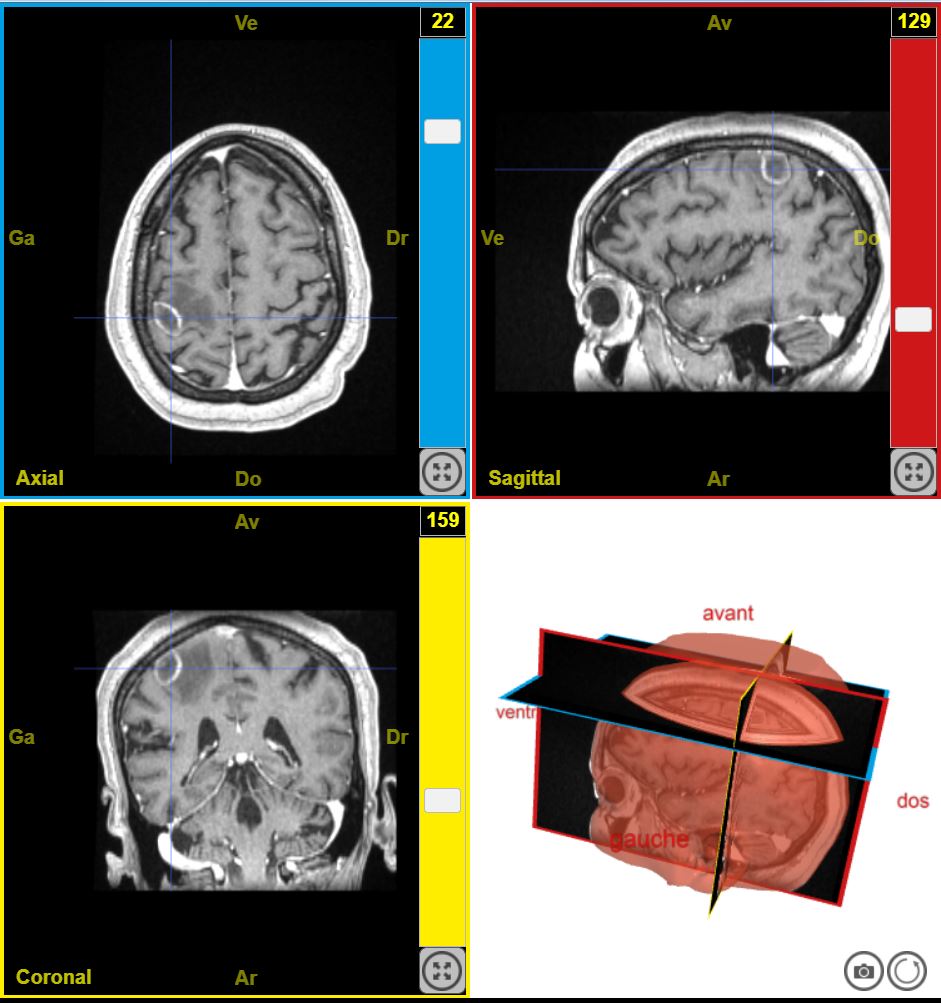

12223PathologieTumeurDeficitMoteurDroit T1